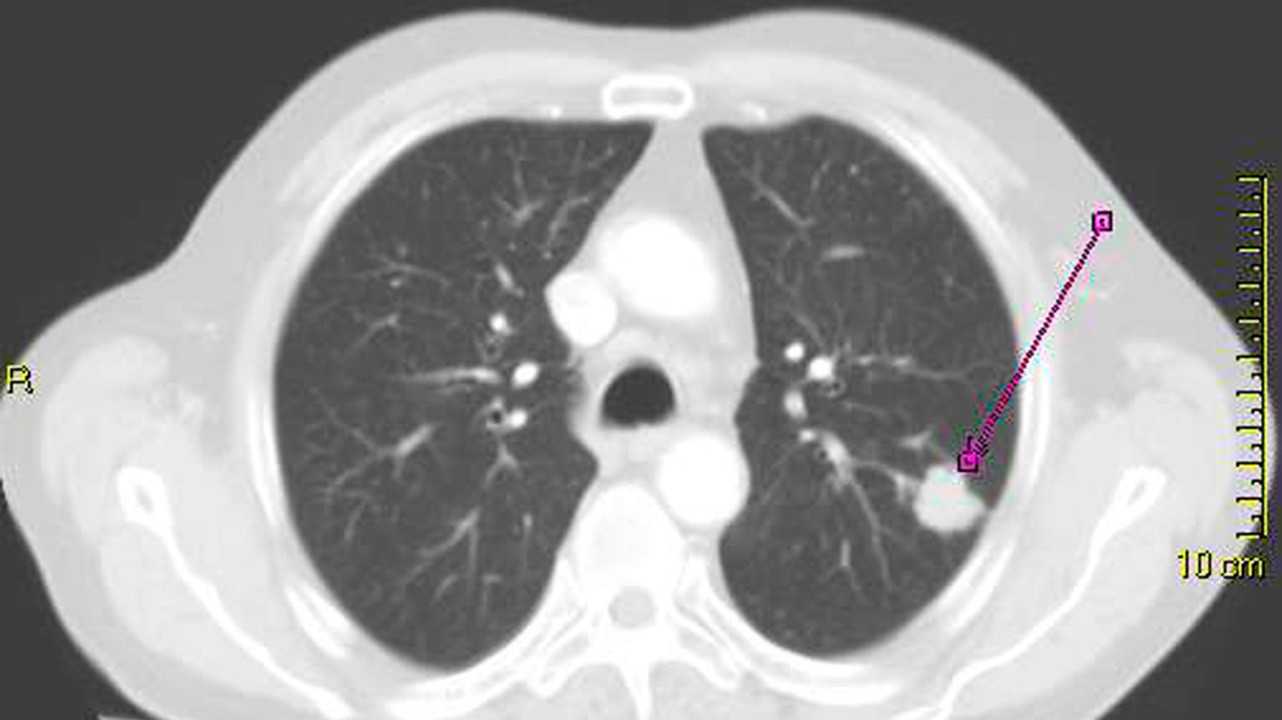

Для постановки диагноза может потребоваться проведение компьютерной томографии (КТ) или магнитно-резонансной томографии (МРТ) легкого.

Снимок КТ с опухолью в легком. Фото: Lange123 / (CC BY-SA 3.0)

Самые современные методы диагностики применяются на ранних стадиях процесса для уточнения диагноза и включают:

- Многослойную спиральную компьютерную томографию, которая позволяет обнаружить опухоли до 1-3 мм

- Позитронно-эмиссионную томографию в сочетании с компьютерной томографией (ПЭТ-КТ), минимальные размеры выявляемой опухоли 5-7 мм.